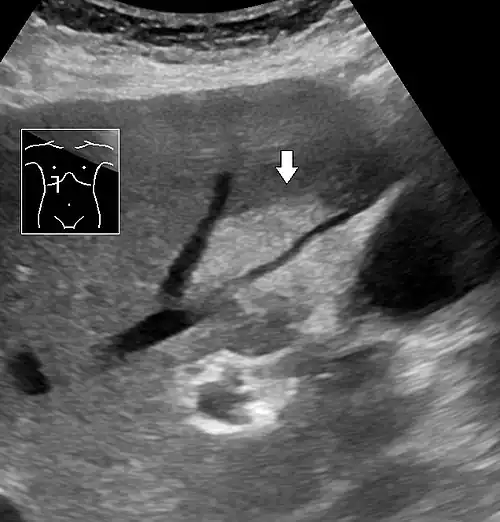

Abdominal ultrasonography of focal steatosis. It is distinguished from a tumor by not compressing the hepatic vein.